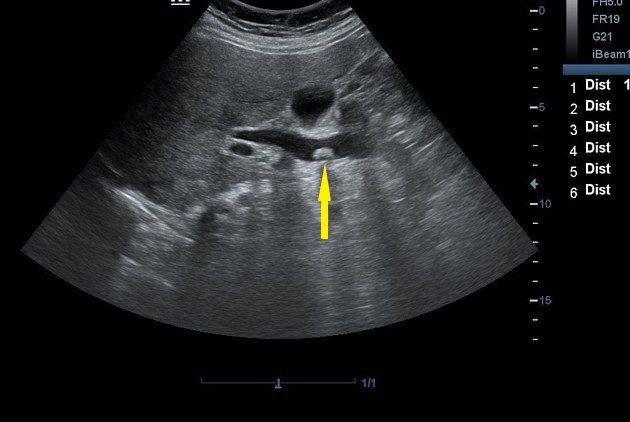

Холедох у ребенка

Холедох у ребенка 110 фотографий